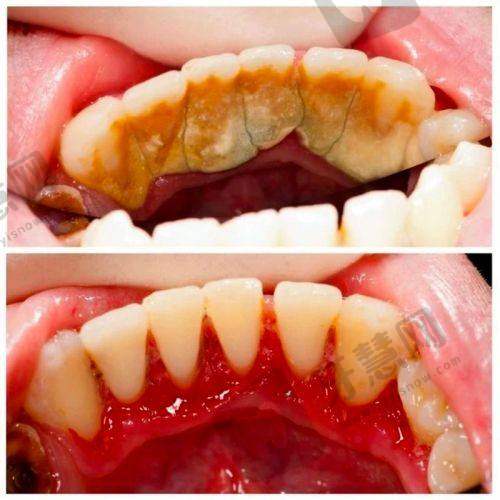

患者对郭佳星医生的评价颇高。有家长带孩子去欢乐口腔(六道口分院)找郭医生补牙,称赞他技术特别好,对待小朋友极有耐心,补牙又快又好,整个过程热情周到,孩子都没有抗拒,有非常棒的补牙体验,同时助理洗牙也仔细干净。还有患者经朋友介绍,带孩子到欢乐口腔做反颌矫正,工作人员推荐了郭主事(推测为郭佳星),并贴心加号。患者表示之前在医院挂号难,而这里可直接预约,医院位置停车方便,对此次就医体验十分满意,认为郭医生值得信赖。